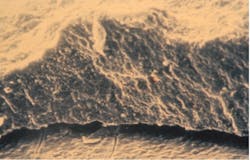

High-powered transmission electron microscopic assay has revealed calculus to be a porous mineralized structure—like a dry sponge—allowing viableMultiple studies in the literature show a relationship between subgingival calculus, inflammation, and microulcerations in the adjacent soft-tissue wall of the periodontal pocket. The bacteria within the calculus have the potential to release potent toxins into the tissues, inciting inflammation and causing the disease to progress. Periodontal pathogens, such as Porphyromonas gingivalis, are capable of reaching the bloodstream through the ulcerated pocket wall and have been found in the brains of patients with Alzheimer’s and in coronary atheromatous plaques.

- Cemental mounds. These sessile elevations on the surface of cementum are the former insertion sites of the collagen fibrils of the periodontal ligament. The underside of calculus has depressions that fit over the mounds, providing minimal retention (figure 3). Light root planing with a curette or ultrasonic scaler is sufficient for removal.

- Fractured calculus. Calculus can chemically bond to the hydroxyapatite crystalline structure of cementum, and that union can be stronger than the cohesive strength within calculus itself.9 When attempting to remove, the calculus can fracture and a basal layer remains firmly attached to the root. Repeated strokes with a scaling instrument result in a “burnished,” or smooth, surface that is often undetectable by a periodontal probe.